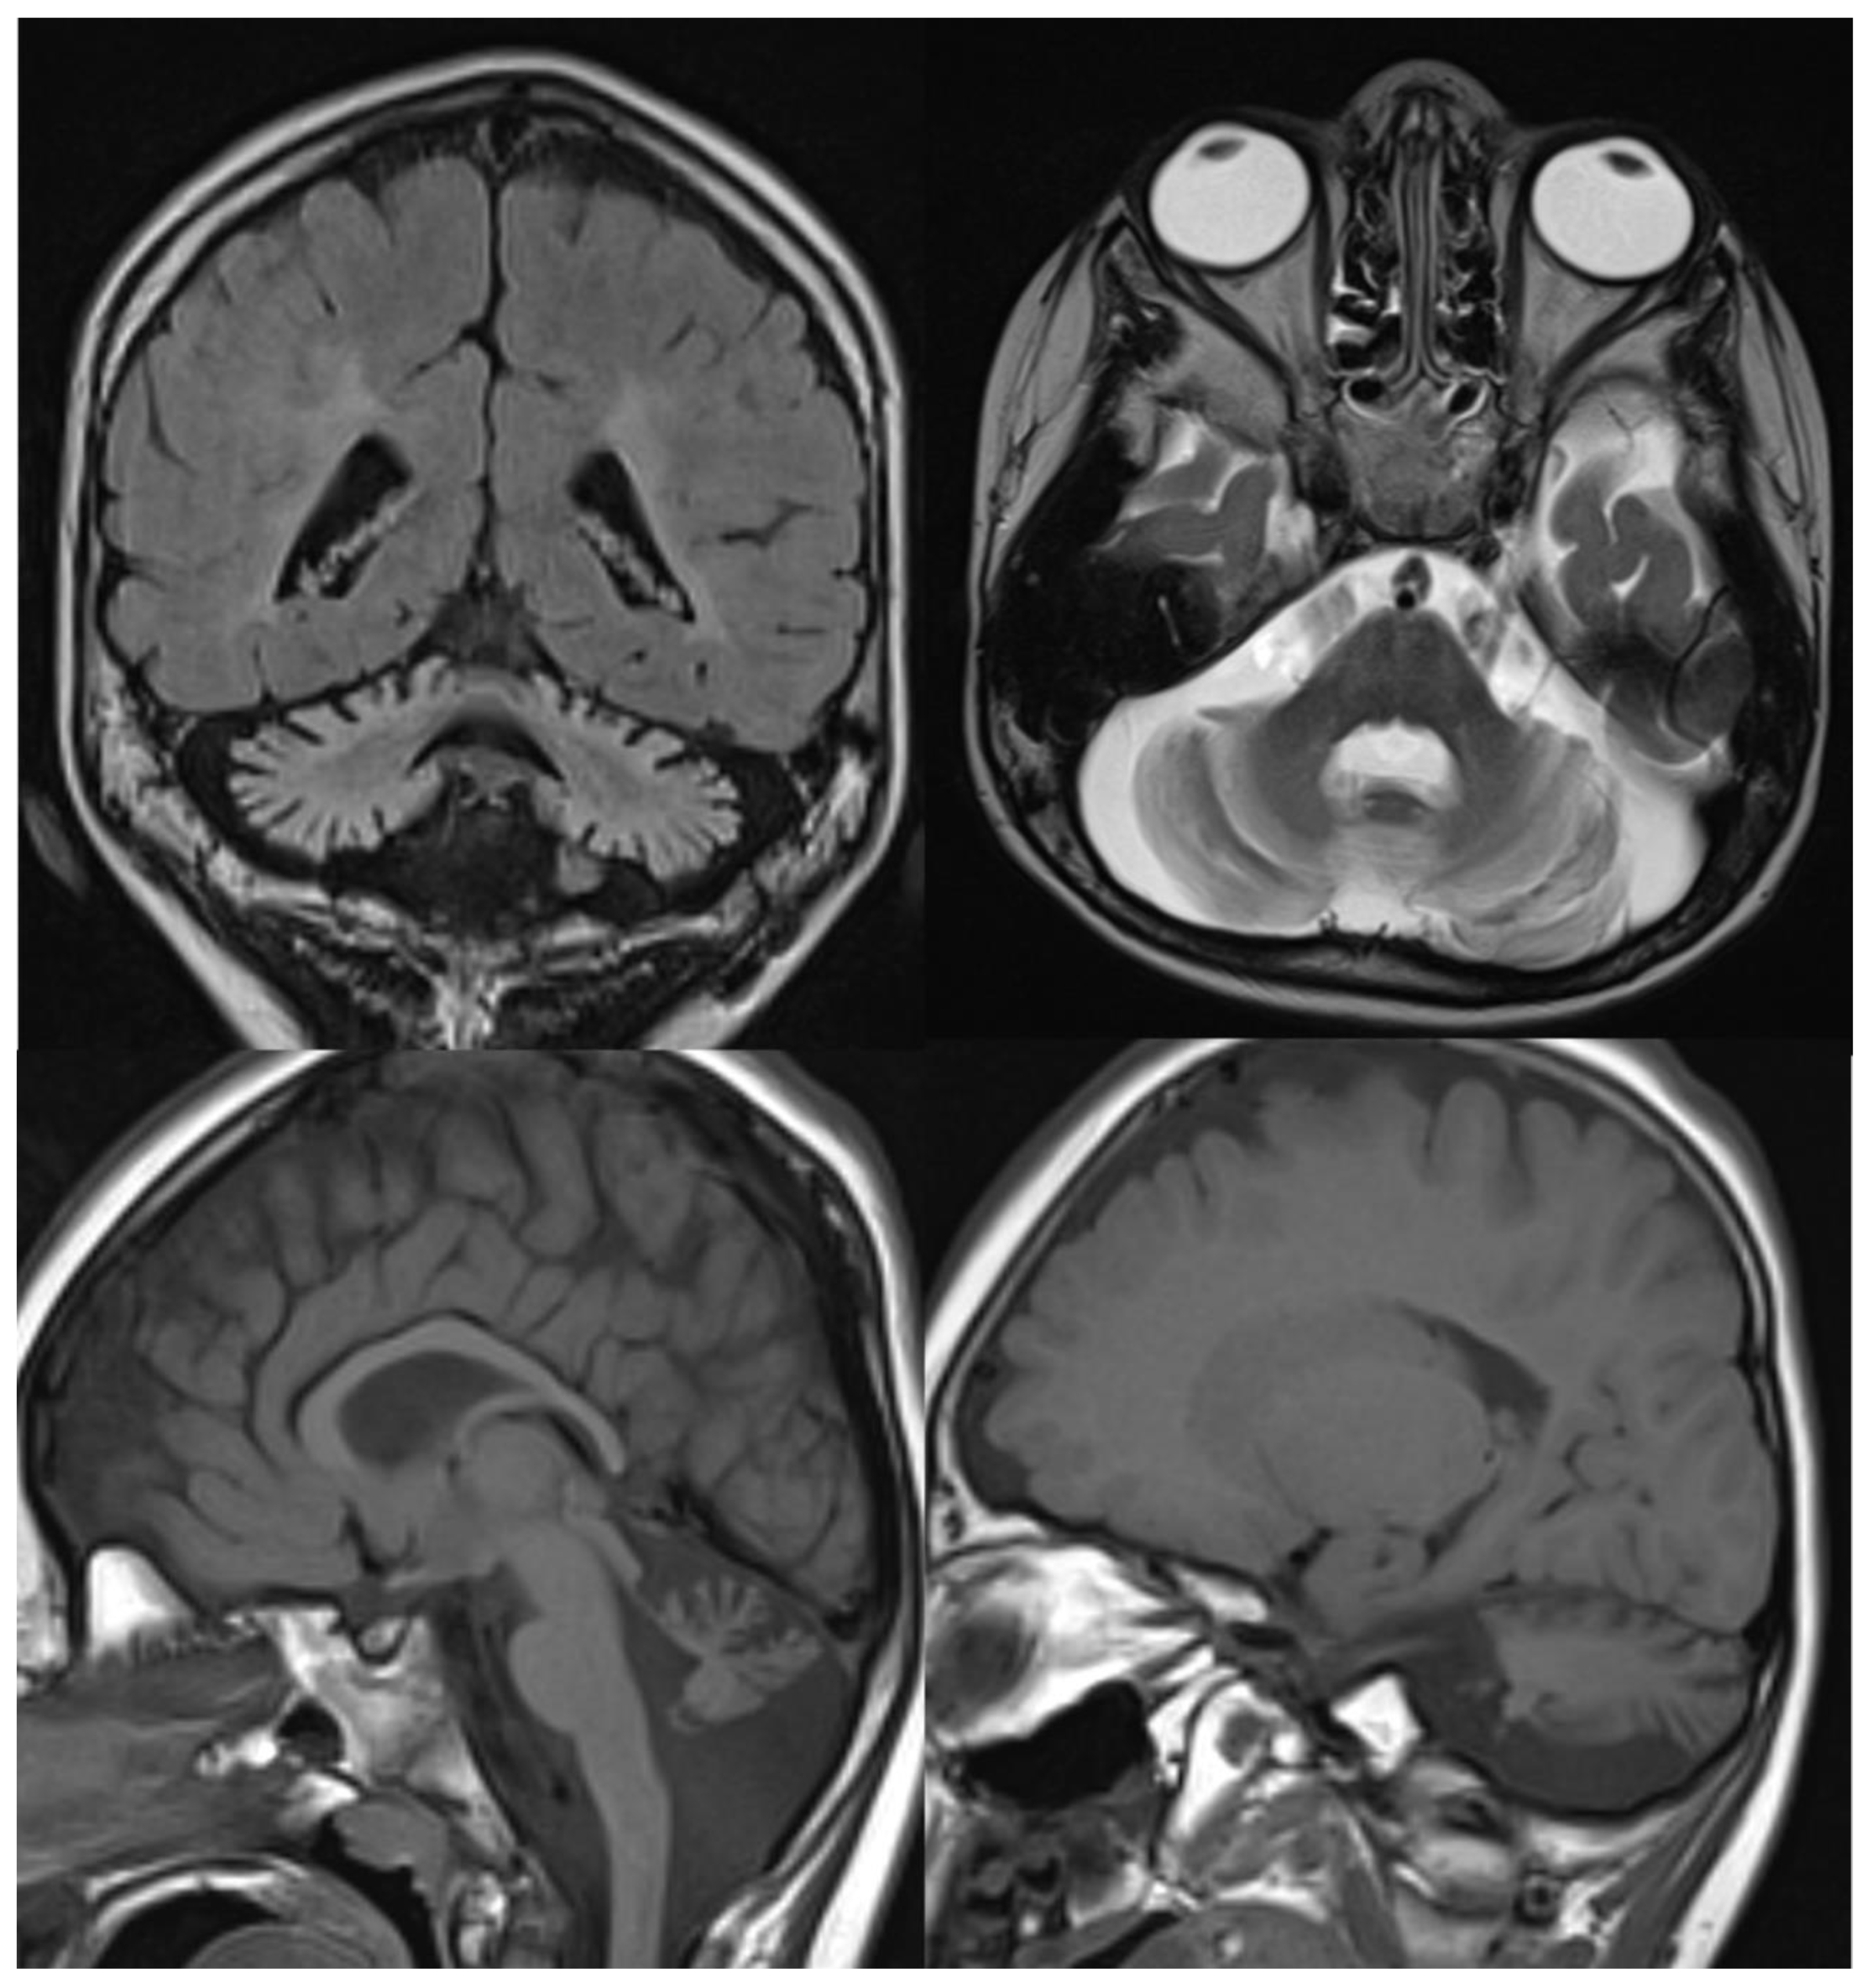

MRI shows global atrophy of the cerebellum, mainly involving the inferior part of the vermis. Associated features are hyperintensity of the cerebellar cortex and dentati nuclei, thinning of the optic chiasm, clava hypertrophy, and, inconstantly, iron deposition in the globus pallidus and the substantia nigra [14,15] (Figure 3).

Figure 3.

INAD. Brain MRI scan of a 6-year-old girl. MR images demonstrate global cerebellar atrophy and cerebellar cortex hyperintensity, very thin optic chiasm, and “clava hypertrophy” due to enlargement of gracile and cuneate nuclei by axonal swellings and spheroids.

MRI studies show characteristic features of the disease: atrophy of the superior cerebellar vermis and cervical spinal cord with bulky pons and increased thickness of the middle cerebellar peduncles. On T2w-FLAIR images, the pons shows a subtle hyperintensity (mainly in the raphe and lateral aspects) and exhibit hypointense stripes, acknowledged as the corticospinal tract (CST). Similar hypointensity is also observed in the medial lemnisci [4]. Thinning of the corpus callosum and a rim of T2-hyperintensity around the thalami are also frequent findings (Figure 4).

Figure 4.

ARSACS. Brain MRI scan of a 15-year-old boy. The images demonstrate the superior vermis and cervical spinal cord atrophy, bulky pons, and a thin corpus callosum. T2-wi at the level of the pons show diffuse, slight hyperintensity mostly in the lateral part of the pons and in the raphe. Corticospinal tracts are visible as hypointense parallel, thin stripes. The medial lemnisci also presented similar hypointensity. Note in the last image a rim of T2-hyperintensity around the thalami.